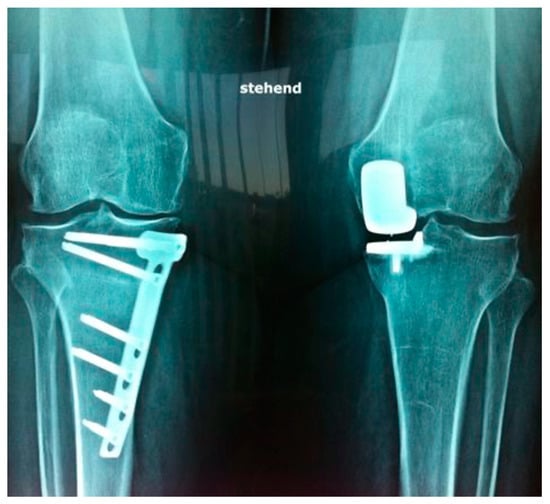

3.3. Radiological Outcome/OA Progression